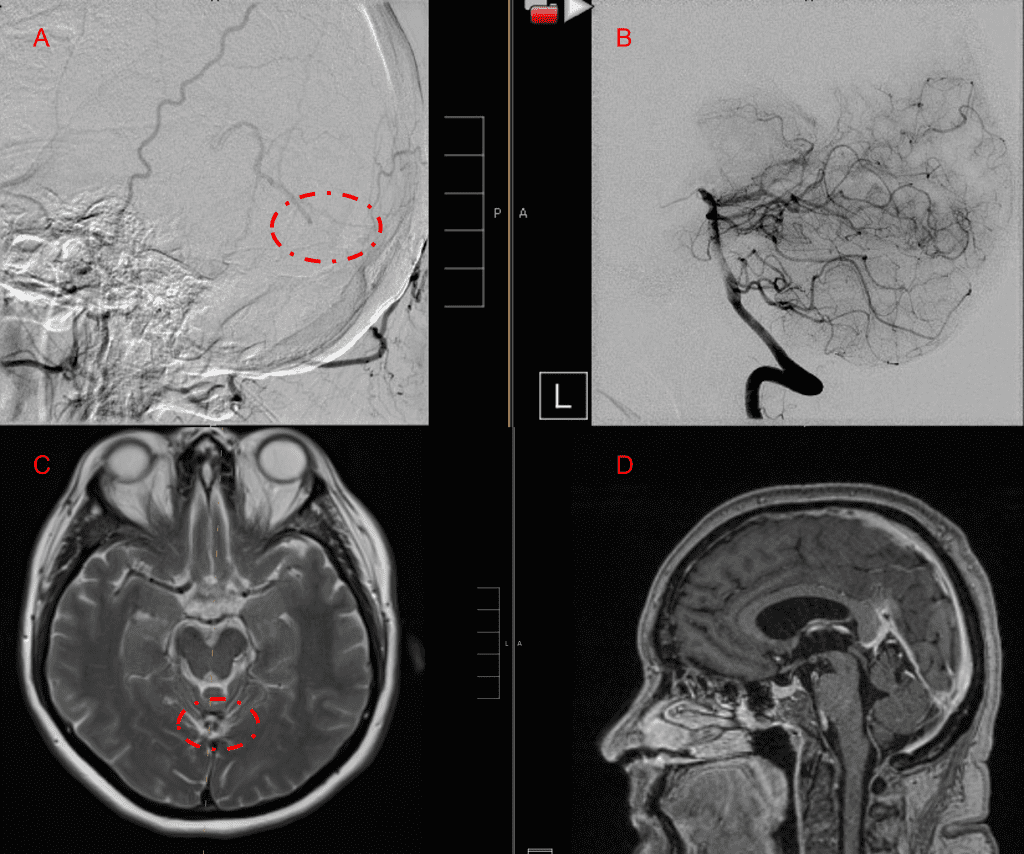

Figure 3. Right ECA AP and Lateral angiograms Pre (A and B) and Post NBCA embolization (C and D) Demonstrate near complete obliteration of right Occipital and Middle Meningeal Artery Fistulas